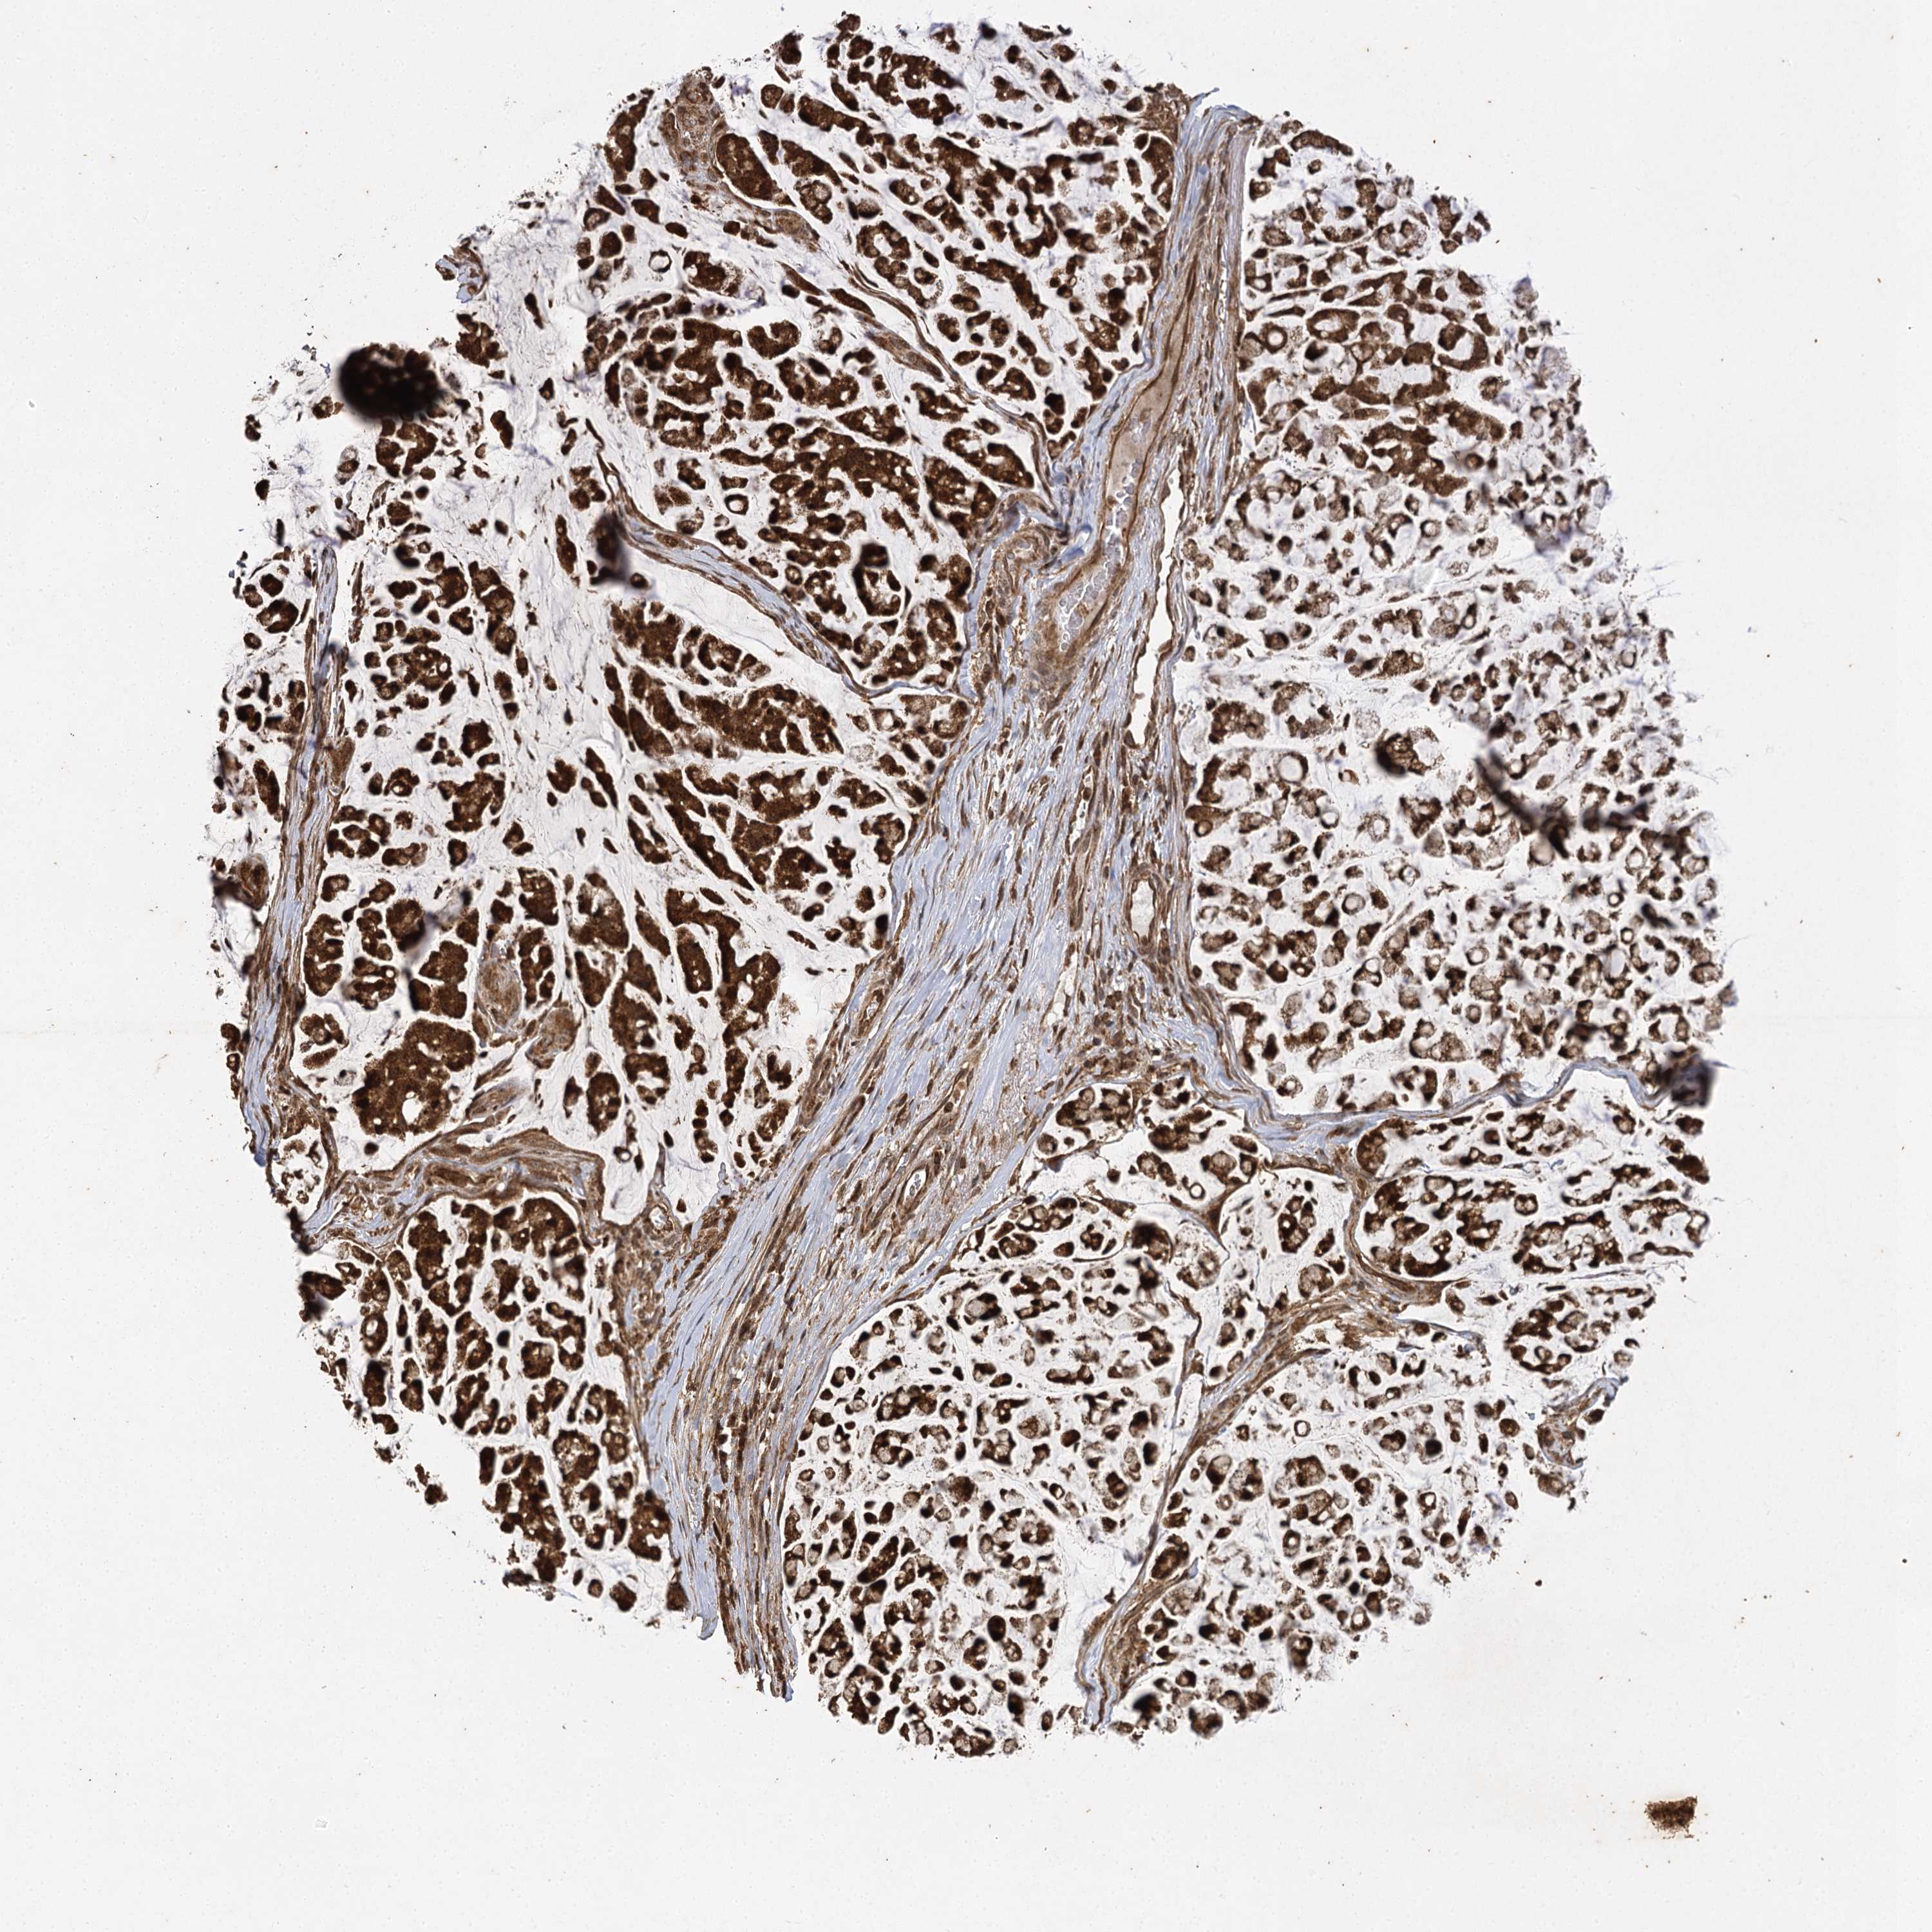

STOMACH CANCER - Protein expressioni

A mouse-over function shows sample information and annotation data. Click on an image to view it in a full screen mode. Samples can be filtered based on level of antibody staining by selecting one or several of the following categories: high, medium, low and not detected. The assay and annotation is described here.

Note that samples used for immunohistochemistry by the Human Protein Atlas do not correspond to samples in the TCGA dataset.

Antibody stainingi

Antibody staining in the annotated cell types in the current human tissue is reported as not detected, low, medium, or high, based on conventional immunohistochemistry profiling in selected tissues. This score is based on the combination of the staining intensity and fraction of stained cells.

Each image is clickable and will lead to virtual microscopy that enables deeper exploration of all samples and also displays staining intensity scores, fraction scores and subcellular localization as well as patient and tissue information for each sample.

Antibody HPA013162

Antibody HPA036652

Antibody CAB032830

Staining

High

Medium

Low

Not detected

Intensity

Strong

Moderate

Weak

Negative

Quantity

>75%

75%-25%

<25%

None

Location

Nuclear

Cytoplasmic/membranous

Cytoplasmic/membranous,nuclear

Adenocarcinoma, NOS

Adenocarcinoma, High grade